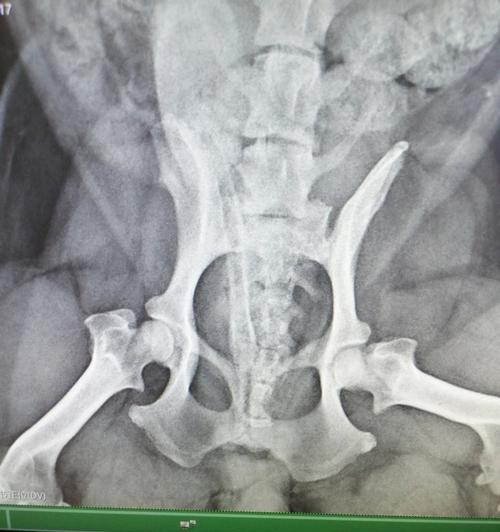

狗狗腿髋坏死病因分析及治疗方案全解析 狗狗腿髋坏死严重影响宠物生活质量,早期发现可通过药物治疗和康复理疗缓解症状。严重情况下需采用髋关节手术或人工关节置换,术后配合专业康复训练能显著改善狗狗行动能力,主人需提供持续关爱和耐心护理。 养护知识 2026-03-06 02:03 浏览:799